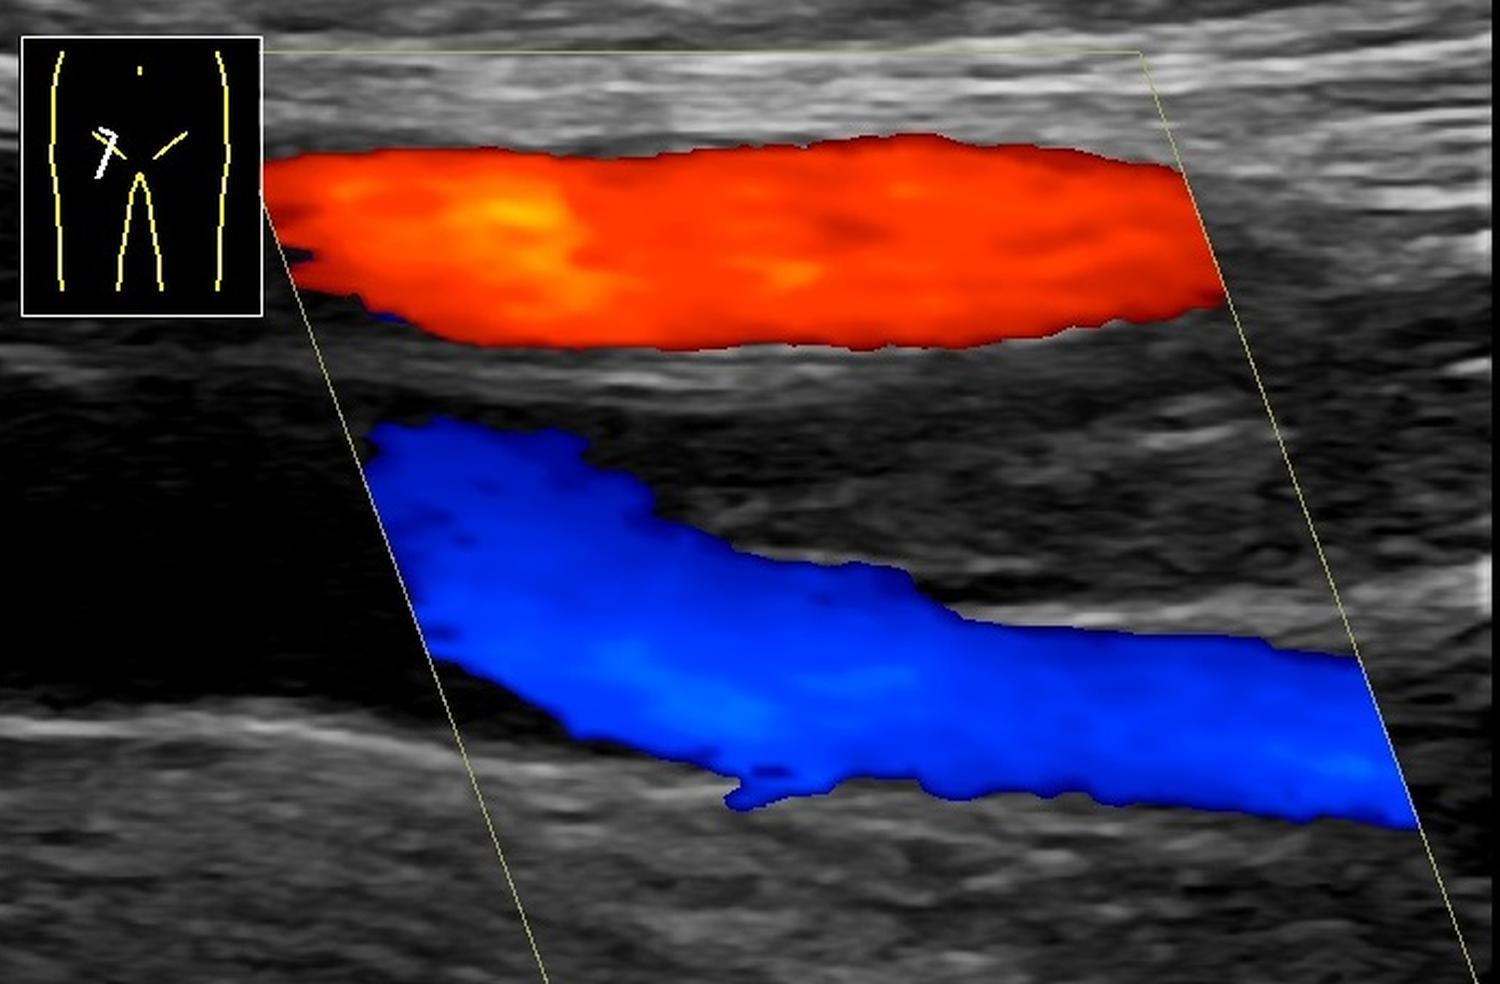

Mélyvénás alsó végtagi trombózis (comb, doppler ultrahangfelvétel)

A combartéria (piros) alatt az elágazó combvéna (kék) trombózisa. A színes területeken akadálytalanul folyik a vér, a köztük lévő, elágazás utáni szakaszon látható a trombus okozta elzáródás. (doppler ultrahang; szerző: Mikael Häggström, M.D., Wikimedia Commons nyomán)